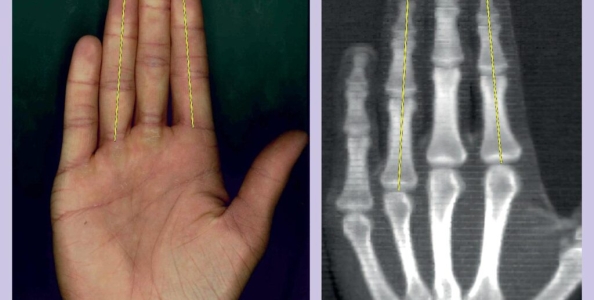

Per la ricerca gli studiosi hanno preso in esame un campione di 176 individui. Nel laboratorio della High Point University in North Carolina hanno misurato la lunghezza dell’indice e dell’anulare, prima con il metro e poi con i raggi-x.

Il rapporto tra queste lunghezze, secondo la scienza odierna, può predire alcuni aspetti psicologici dell’individuo, di cui il più importante è l’esposizione del soggetto al testosterone durante la gravidanza.

In base ai risultati ottenuti, un basso rapporto tra lunghezza del dito indice e lunghezza del dito anulare (la cosiddetta ‘2D to 4D ratio’ nei paesi angolofoni) indica che il soggetto gode di buona fortuna, in particolare se è un uomo.